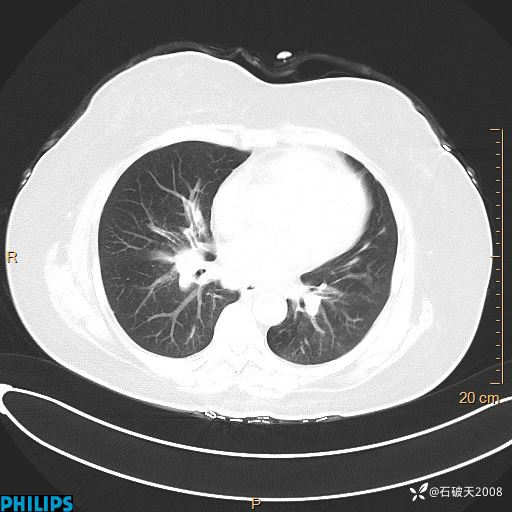

肺结节病?纵膈型肺癌?淋巴瘤?有点意思,欢迎围观

女 52岁 主 诉:咳嗽10余天,咳痰2天。

现病史:10余天前无明显诱因出现咳嗽,呈阵发性干咳,伴咽喉部发痒,无咽痛,无咳痰,无鼻塞、流涕、打喷嚏,无发热、畏寒、寒颤,无头痛、头晕,无胸闷、胸痛,无反酸、烧心,无腹痛、腹泻,无尿频、尿急,无皮疹等,在当地诊所求治,给予口服药物治疗(具体不详),病情无好转。遂在当地社区卫生服务中心开具口服药物治疗(具体不详),疗效欠佳。2天前出现咳痰,在我院门诊求治,行胸部CT提示肺部感染,建议住院,患者要求口服药物治疗,目前仍咳嗽、咳白色粘痰,白天量多,夜间自觉喉部喘鸣音,遂再次来院就诊,以“肺部感染”为诊断收入院。发病以来,神志清,精神可,饮食可,夜间睡眠差,大小便正常,近期体重无明显变化。

纵隔窗